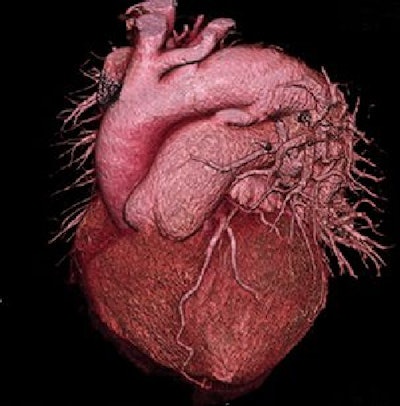

Quiz 1

Three-dimensional CT angiography of the heart in a 53-year-old patient with shortness of breath.

By Dr. Stephan Achenbach, Friedrich-Alexander, University Erlangen-Nürnberg, Germany.